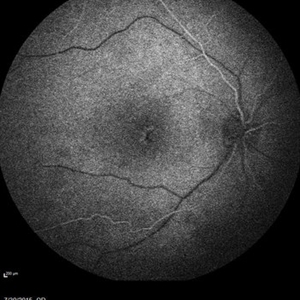

Retinal Dystrophy of 24-Year-Old Male/ IR OD

Nov 25 2015 by Zach Dupureur

Fluorescein angiography of a 24-year-old male. Juvenile retinoschisis on OCT. FA shows outer retinal staining. Could be associated with Goldman Farve Syndrome.

Photographer: Zach Dupureur OCT-C

Imaging device: Heidelberg Spectralis

Condition/keywords: Goldmann-Favre Syndrome, juvenile retinoschisis, retinal dystrophy